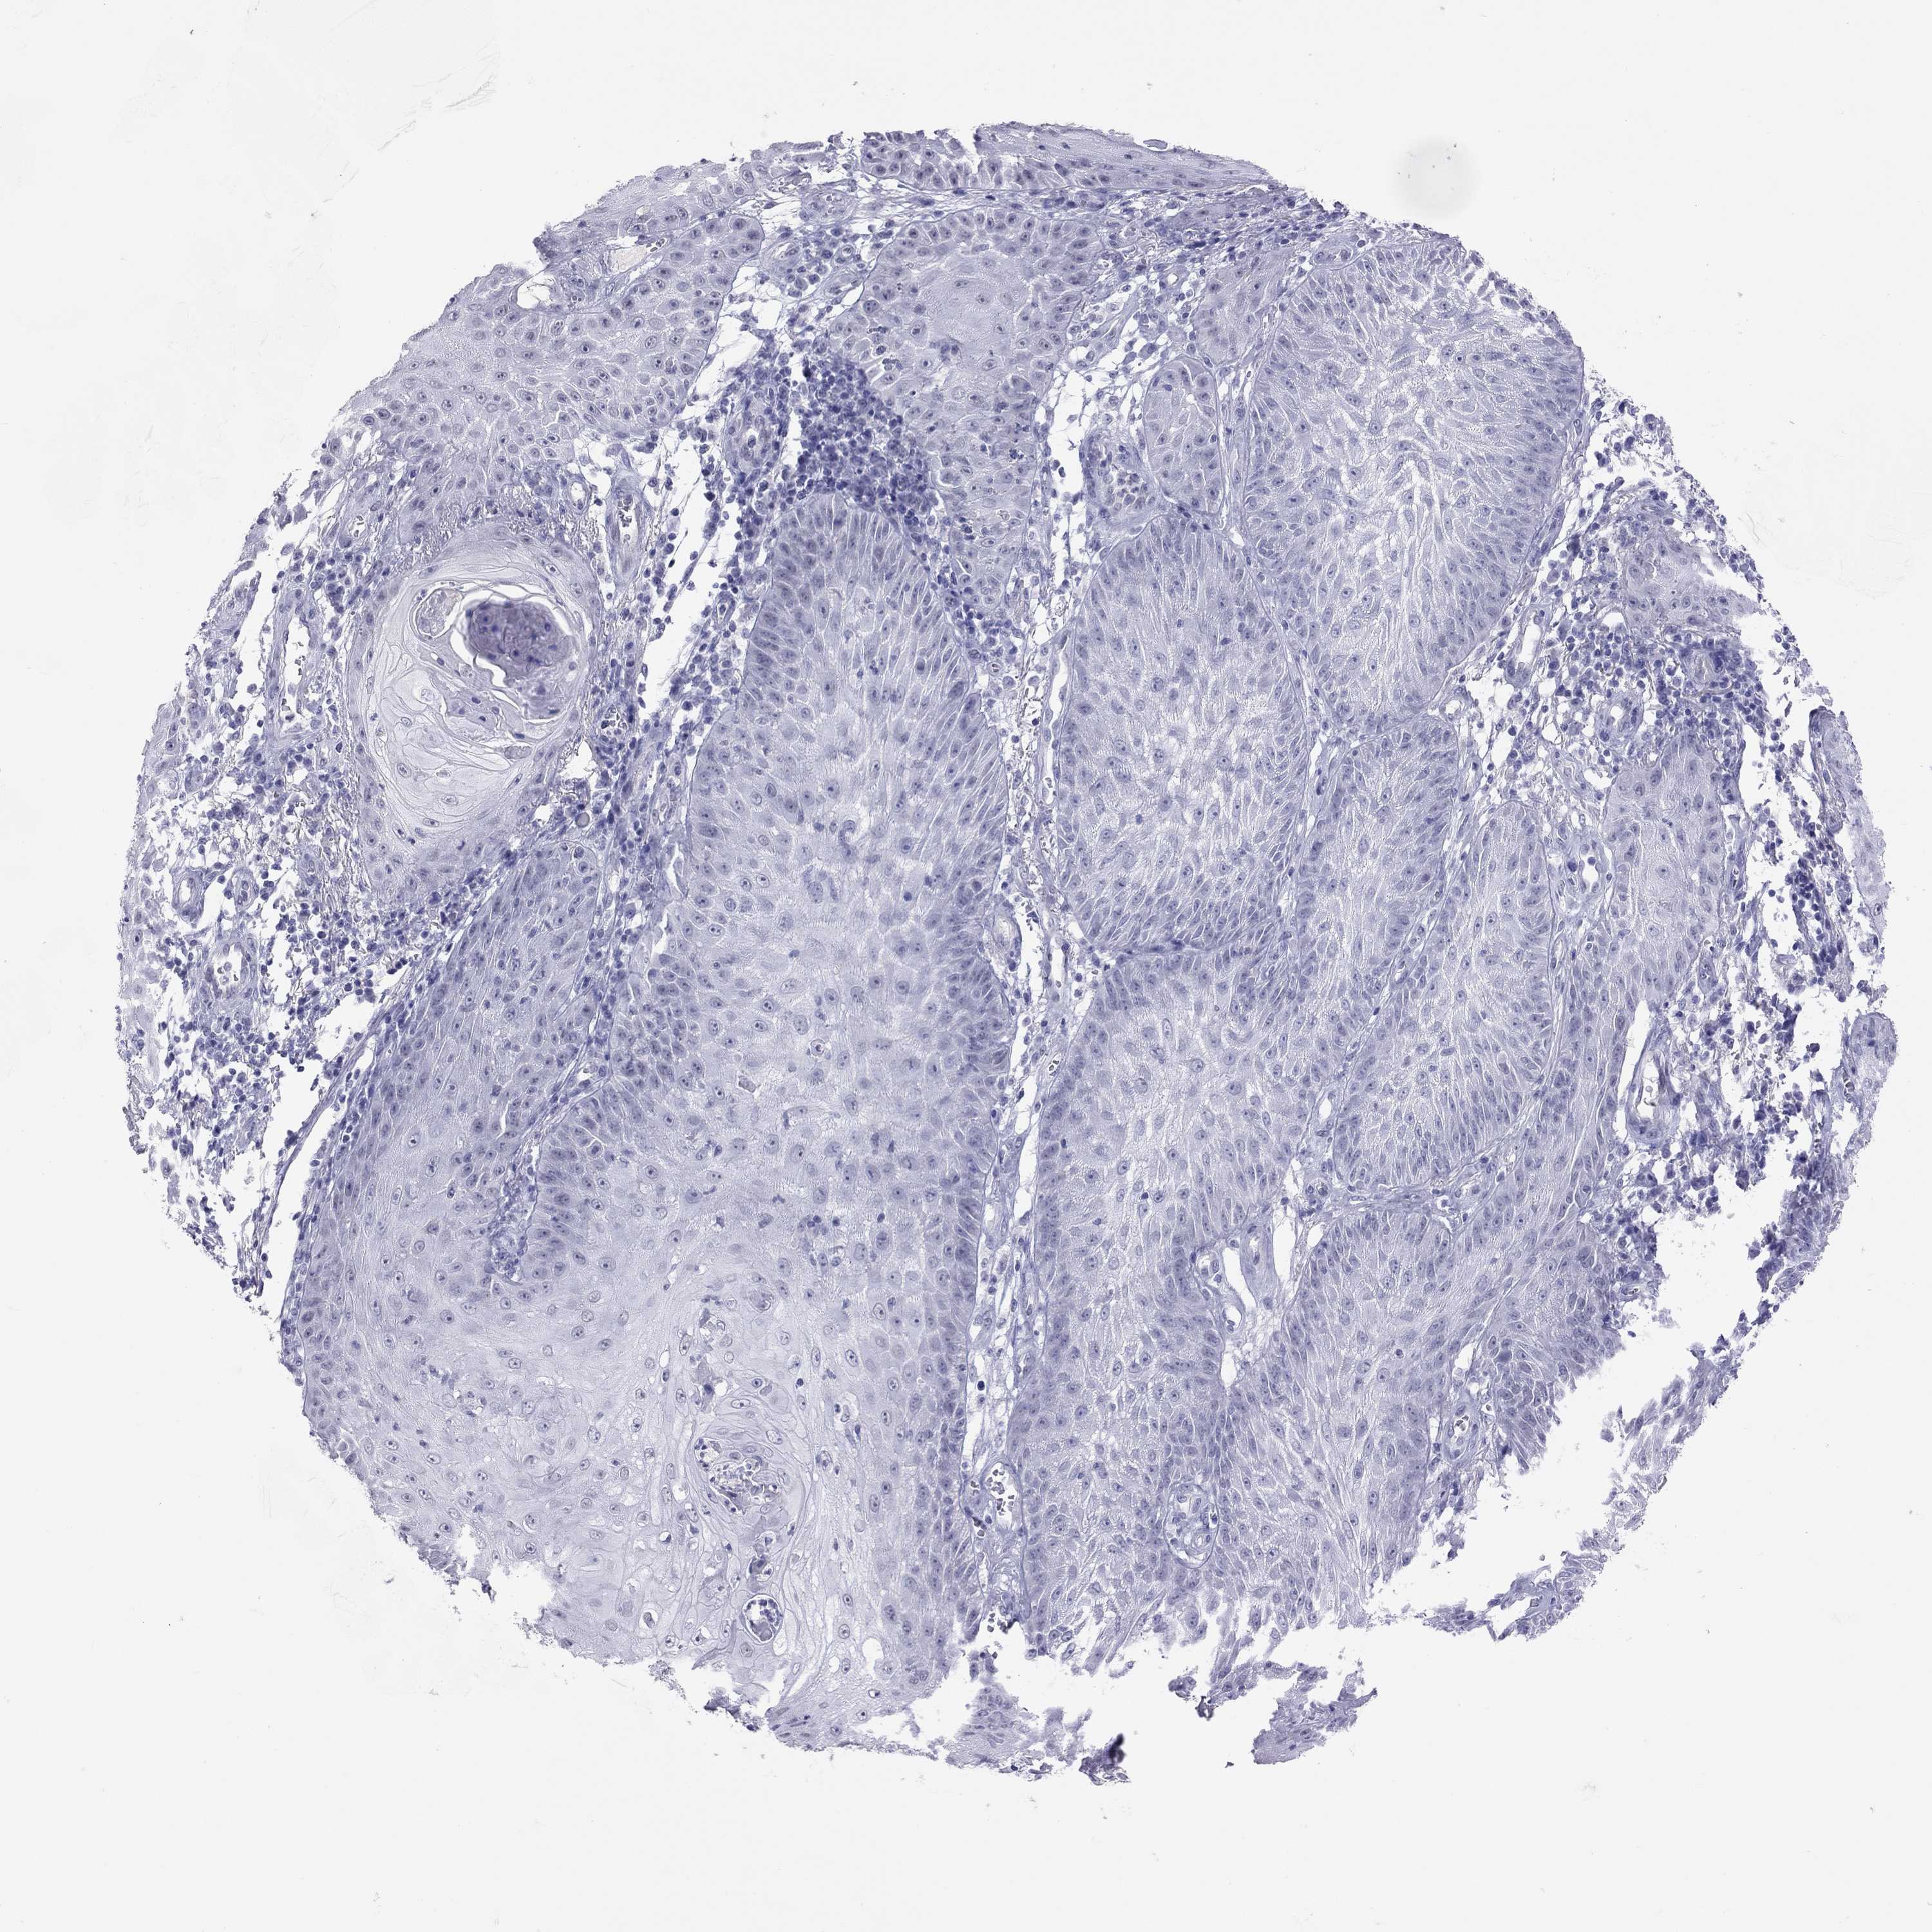

Basal cell and squamous cell cancer

SKIN CANCER - Protein expressioni

A mouse-over function shows sample information and annotation data. Click on an image to view it in a full screen mode. Samples can be filtered based on level of antibody staining by selecting one or several of the following categories: high, medium, low and not detected. The assay and annotation is described here.

Each image is clickable and will lead to virtual microscopy that enables deeper exploration of all samples and also displays staining intensity scores, fraction scores and subcellular localization as well as patient and tissue information for each sample.

Antibody HPA077658

Basal cell carcinoma

Squamous cell carcinoma, NOS